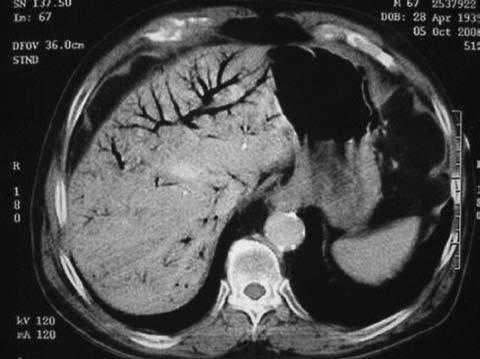

La isquemia mesentérica no oclusiva es una complicación grave con una importante morbilidad en los pacientes sometidos a programas de hemodiálisis1. Presentamos el caso clínico de un varón de 76 años sometido a un programa de diálisis desde hacía 5 años que acudió a urgencias por presentar tras diálisis un importante dolor abdominal difuso de 4 h de evolución; presión arterial, 80/43 mmHg; pulso cardíaco, 115, y temperatura, 37,3 °C; la exploración física reveló claros signos de irritación peritoneal. Se realiza una tomografía computarizada abdominal que muestra gas en las venas porta y mesentérica superior sin neumatosis intestinal (fig. 1). Con la sospecha de necrosis intestinal se realiza una laparotomía media exploradora en la que sólo se observa dilatación del intestino delgado y una pequeña cantidad de líquido ascítico claro en la pelvis, con el pulso de las arterias mesentéricas palpable, sin necrosis ni perforación intestinal.

Fig.1.Tomografía computarizada de un paciente de 76 años que presenta neumatosis portal tras una sesión de hemodiálisis.